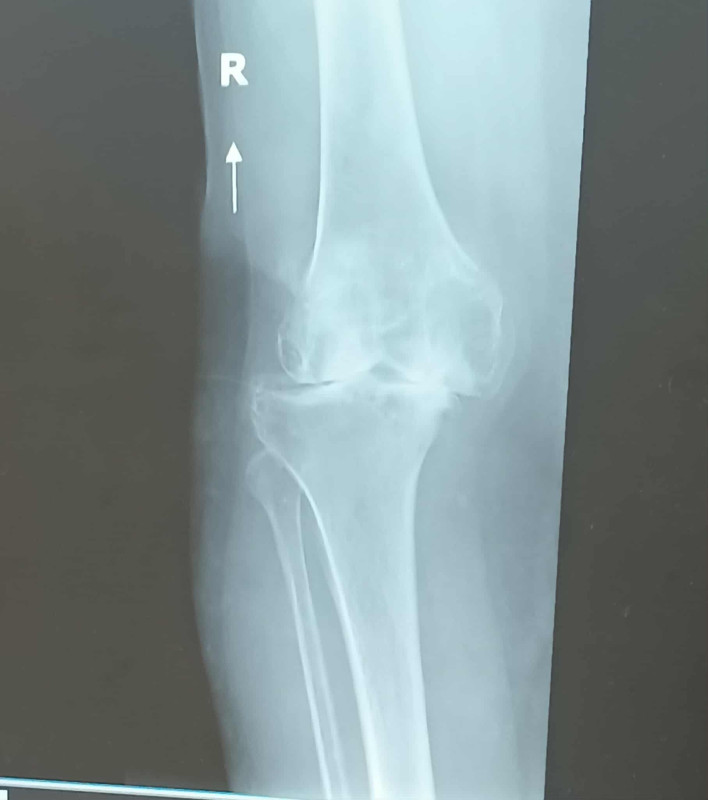

My name is Valerie Solis. I am a 53yo female that has been dealing with a long time injury to my right knee. In 2005, I was in a major car accident that led to me needing surgery in my right knee. Surgery was completed within 3 months of the accident but it did very little to help. I was able to walk without any assistance but I was always in pain. I went to several Orthopedic surgeons, had several different injections, 3 worked but just for a short period of time and not like they should have. Finally, I received the news in 2012, a right total knee replacement. However, since I was able to walk without any assistance, they would not do the surgery because of my age and I would more than likely have to have another replacement done within 10-15 years. “Come back when you can't stand the pain or can't walk anymore”. Well that time has arrived. My knee was so misaligned, contained no cartilage, multiple bone spurs, arthritis, calcium deposits and I was in constant pain. My doctor was shocked that I was able to still walk (short distances only).

I could not wait any longer and have recently underwent a total right knee replacement on August 22, 2025. I am currently at 3 weeks post surgery and I can already tell the difference. I am currently doing in home physical therapy and I have began walking, going a bit further everyday. Soon, I will be able to attend family functions, performances of my children and grand children and just being able to go to the mall without having my knee stop me like it did so many times before. I am even looking forward to when I am able to walk up a flight of stairs.